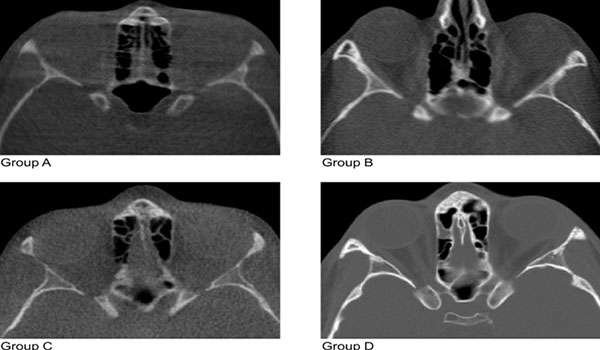

CBCT (Cone Beam Computed Tomography) is a specialized type of X-ray equipment used when regular dental or facial X-rays are not sufficient. It uses a cone-shaped X-ray beam to create detailed 3D images of the bone, soft tissues, nerve pathways, and dental structures in a single scan. This technology is particularly useful for evaluating complex cases and planning surgical procedures.

• Detailed 3D Imaging: Provides a complete view of the bone, teeth, and soft tissues, enabling precise diagnosis and treatment planning.

• Accurate Diagnosis: Enhances the accuracy of diagnosing conditions such as bone abnormalities, infections, and complex tooth structures.